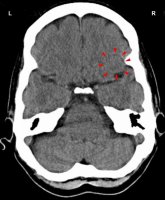

This CT scan shows an active Hamer Focus with a sharp ring configuration on the right side of the pre-motor sensory cortex (view the GNM diagram) for the left paranasal sinuses, linked to a scent or stink conflict related to a partner if the person is left-handed; for a right-handed person the conflict is associated with his/her mother or child.